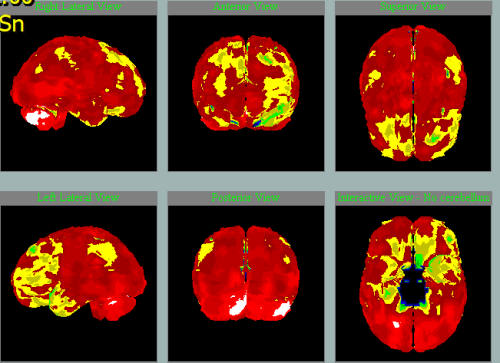

V letech je možné vidět přibývání hypoperfúze a tedy progresi:

2011

2014

2020